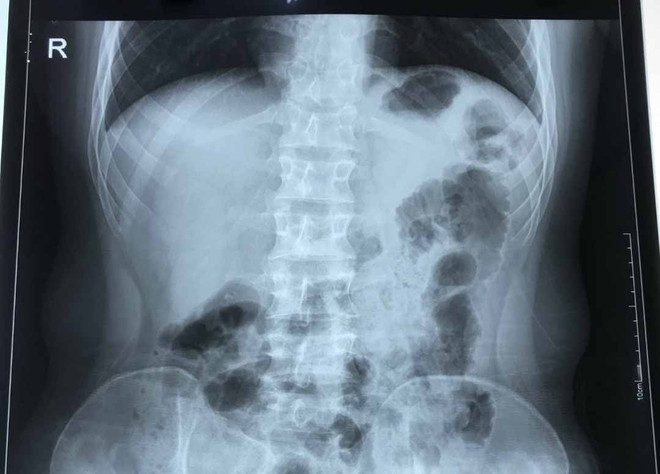

Hà Nội: Nam thanh niên viêm ruột thừa cấp có trái tim bên phải ảnh 1Phim chụp của bệnh nhân viêm ruột thừa cấp có phủ tạng đảo ngược hoàn toàn cực kỳ hiếm gặp. (Ảnh: PV/Vietnam+)

Khi có kết quả siêu âm, chụp Xquang, bệnh nhân được chẩn đoán viêm ruột thừa. Có một điều khiến các bác sỹ bất ngờ, đó là hình ảnh trái tim trong lồng ngực bệnh nhân H. ở vị trí đảo ngược so với người bình thường.

Theo các chuyên gia, đảo ngược phủ tạng (situs inversus, situs transversus hoặc oppositus) là tình trạng bẩm sinh trong đó các cơ quan nội tạng trong ngực, bụng đảo ngược phản chiếu theo mặt phẳng đứng dọc so với vị trí bình thường. Tình trạng đảo ngược phủ tạng có thể hoàn toàn hoặc chỉ một vài cơ quan đơn thuần.

Đây là một dạng dị tật có tính di truyền gene lặn tương đối hiếm gặp, với tỷ lệ khoảng 1/10.000 dân, trong đó có khoảng 5-10% có dị tật tim bẩm sinh, còn lại có cuộc sống hoàn toàn bình thường, không ảnh hưởng đến sức khỏe người bệnh./.